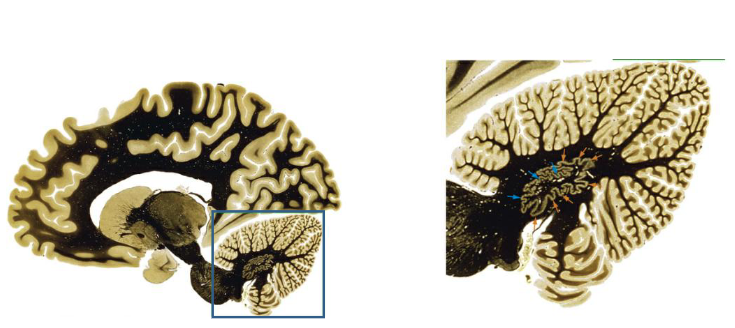

Folia

The surface of the cerebellum is covered with folds called folia. The folia greatly increase the surface area of the cerebellar cortex